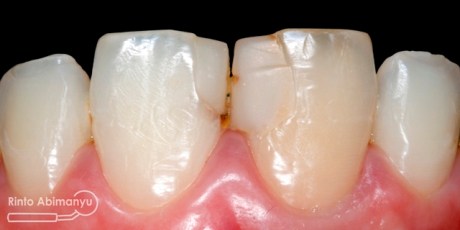

Tambalan lama dibongkar dan seluruh jaringan karies sekunder dibuang, kemudian tepi kavitas labial dibuatkan bevel…

Setelah tambalan dibongkar dan dibuatkan bevel

Gigi-gigi kemudian dietsa dan dibonding, penambalan menggunakan resin komposit Palfique LX5 (Tokuyama) shade OPA2, OA3, A3… Pada kasus ini saya tidak memakai cetakan silikon untuk membantu membentuk outline gigi, hanya mengandalkan seluloid strip..

Selesai penambalan dan sebelum dilakukan konturing dan pemolesan